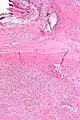

Micrograph of a solitary fibrous tumor. H&E stain.